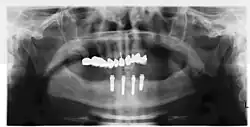

Four mandibular implants

Four lower implants to retain a complete denture with novaloc abutments

Panorex radiograph showing implants

Xray of four Straumann implants and abutments

When a removable denture is worn, retainers to hold the denture in place can be either custom made or "off-the-shelf" (stock) abutments. When custom retainers are used, four or more implant fixtures are placed and an impression of the implants is taken and a dental lab creates a custom metal bar with attachments to hold the denture in place. Significant retention can be created with multiple attachments and the use of semi-precision attachments (such as a small diameter pin that pushes through the denture and into the bar) which allows for little or no movement in the denture, but it remains removable.[30]: 33–34  However, the same four implants angled in such a way to distribute occlusal forces may be able to safely hold a fixed denture in place with comparable costs and number of procedures giving the denture wearer a fixed solution.[79]